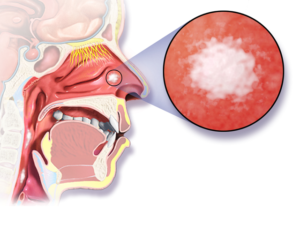

- Рак полости носа и околоносовых пазух. Носовая полость — это пространство позади носа, откуда воздух попадает в горло. Околоносовые пазухи — это заполненные воздухом области, окружающие носовую полость.

- Красное или белое пятно во рту